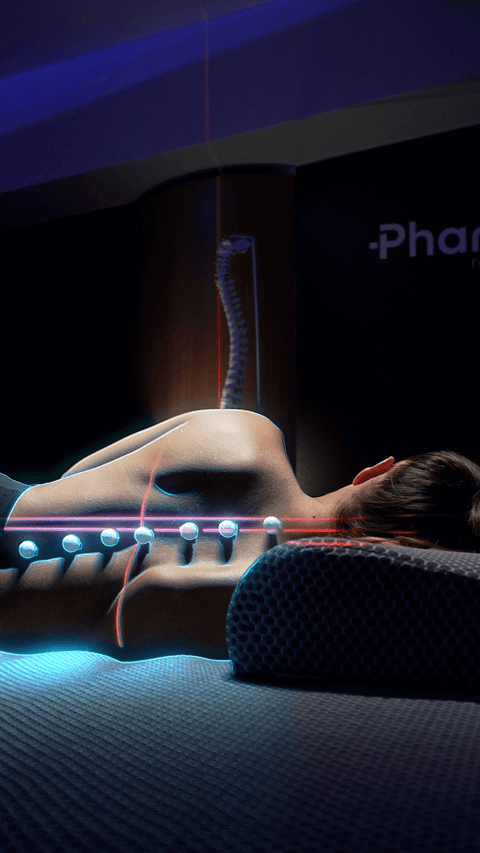

Decompressione vertebrale

Questo test avanzato ad alta precisione ha lo scopo di monitorare la colonna vertebrale prima e dopo l'utilizzo dei nostri prodotti. Confrontando i risultati rispetto ad altri prodotti, i nostri ingegneri biomedici possono valutare con precisione quanto efficacemente l'azione dei dispositivi abbia alleviato la compressione sui dischi e le vertebre.